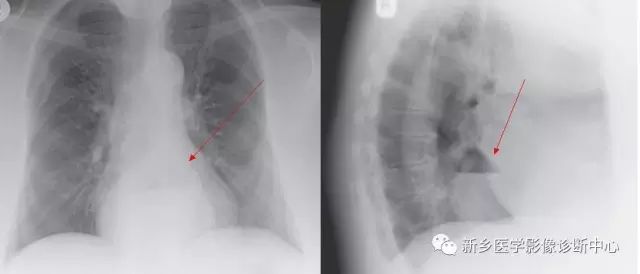

[影像描述]

CT:贲门级部分胃体组织通过食管裂孔进入胸腔内,位于膈上,其上段食管明显扩张。

CT:食管裂孔疝以食管下端纵隔内有疝囊检出为直接征象。疝囊以假肿块样改变为特征,可有软组织密度肿块,也可表现为囊性液体密度影,部分疝囊以食管下端扩张改变为影像表现,经食管裂孔向膈下胃腔延续为主要特点。疝囊外壁光整,内壁可呈锯齿状,可见胃黏膜影像。胃壁充盈好则厚度较薄,疝囊带状管腔扩张样改变,内有潴留食物;充盈不佳者囊壁较厚,表现为软组织团块样影,内有少量液体或气体影。采用CT增强扫描,胃壁与疝囊囊壁均匀一致。